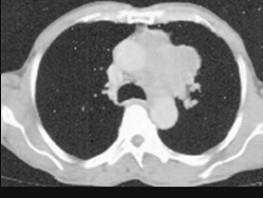

问题 60岁,男,有长期抽烟史,左声带麻痹、声音嘶哑2个月,请结合胸片和CT图.选出最可能的诊断 ( )

选项 A、肺炎 B、肺结节病 C、肺结核 D、尘肺 E、肺癌

答案 E